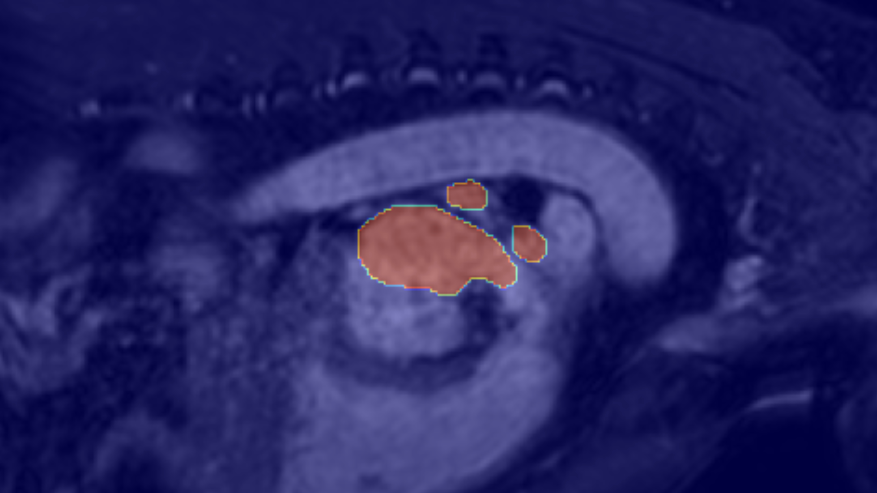

EU-Nets consistently outperform their baseline counterparts, particularly in terms of stability, demonstrating robustness across different cross-validation folds and diverse data distributions. Moreover, integrating MHEX+ introduces only a minimal increase in model parameters (<0.1M). For overall performance comparison, see Table 4, and for individual sample results, refer to the Pred row in Figure 4.

We conducted experiments on the MSD-Heart dataset using 50 randomly selected samples and tested four proposed EU-Nets. Each model’s uncertainty was computed via the MU approach, and the resulting maps were aggregated into a single composite visualization (Fig. 6, last column). For single uncertainty samples, see Figure 4, last row. DEU maps (Fig. 6) were obtained using entropy- and variance-based uncertainty estimation (Section 3.5).